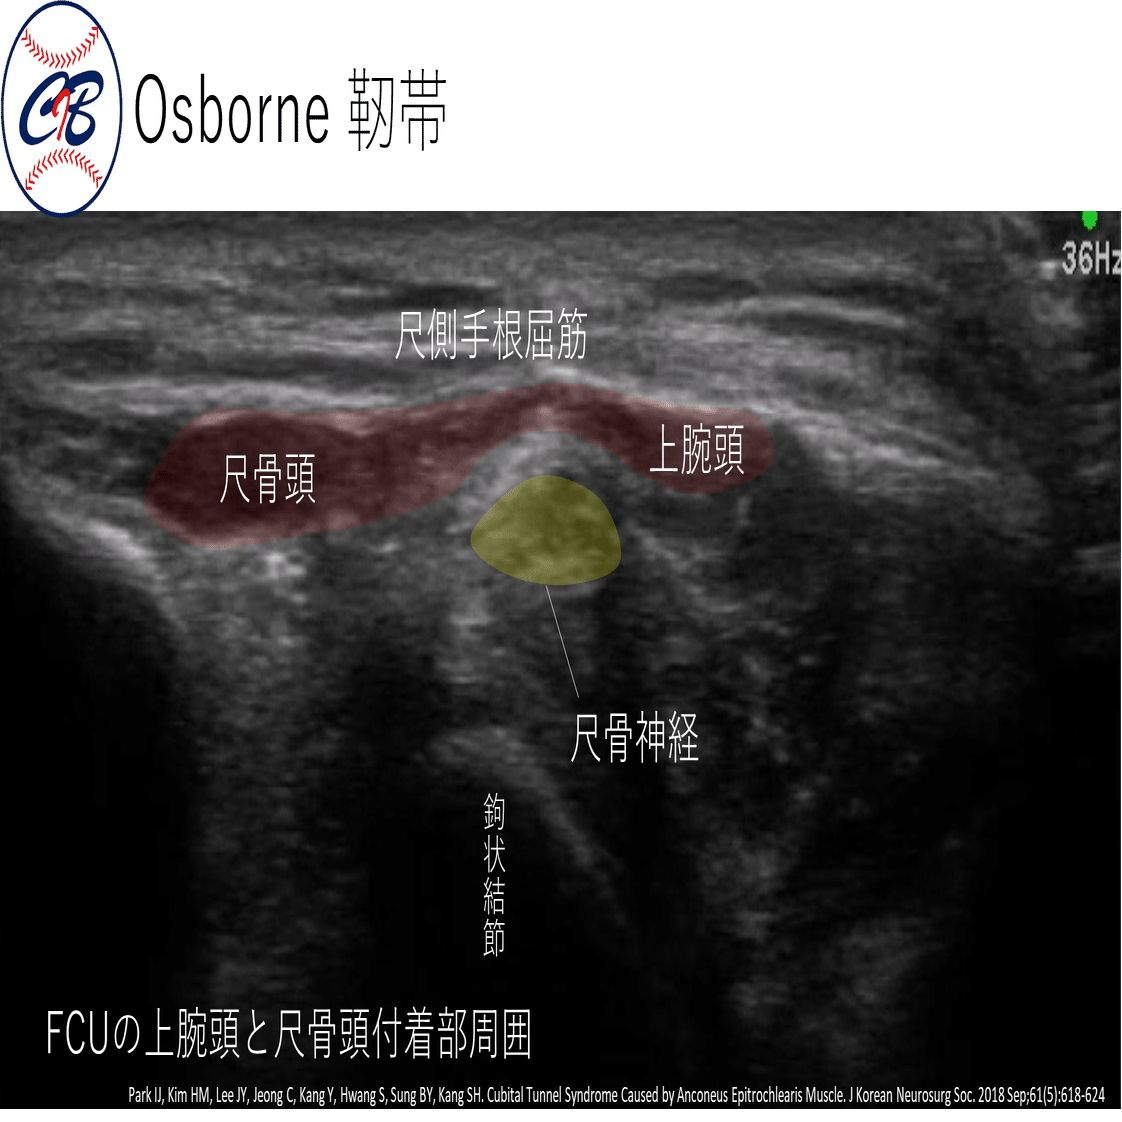

★各絞扼好発部位での Tinel sign~エコーでの見え方~

それぞれの部位がエコーでどのように診れるかを示していきます。

尺骨神経の肘部管の周囲には、3層構造が存在します。

この ”筋筋膜性3層支帯”(the myofascial trilaminar retinaculum:MTR) とよばれているものは、滑走性が重要であるといわれています。